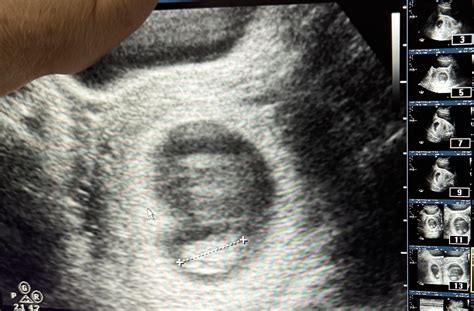

At 9 weeks, the fetus is still very small, but several key features can be visualized:

• Gestational Sac: This is the fluid-filled structure that contains the embryo.

• Yolk Sac: This structure provides early nutrition to the embryo.

• Embryo: The embryo itself, which is about the size of a grape, can be seen with a distinct head and body.

• Fetal Heartbeat: The heartbeat is usually visible and audible, providing reassurance of the fetus’s health.

• Amniotic Fluid: The fluid surrounding the embryo, which protects and cushions the developing fetus.

• Crown-Rump Length (CRL): This is the measurement from the top of the head to the bottom of the buttocks. At 9 weeks, the CRL is typically around 21-27 mm.